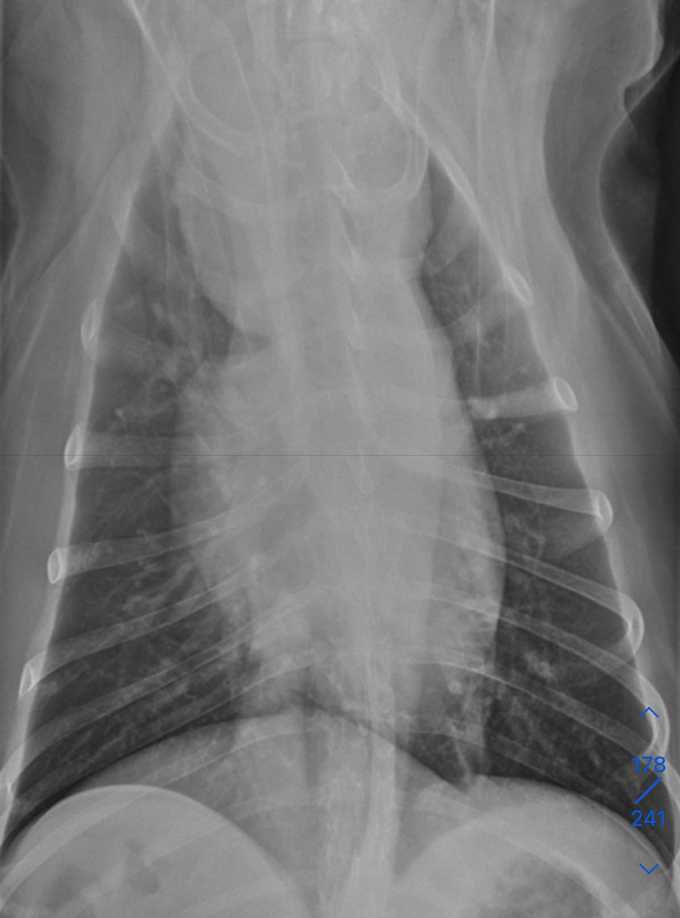

which one pulmonary mass vs extrapleural sign

A

extrapleural sign:

Broad-based mass on the chest wall

Convex shape

Lungs displaced medially